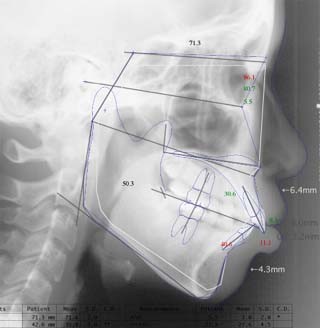

診断名:叢生を伴う上下顎前突

年齢:21歳

上顎前歯、下顎前歯の前突が見られます。大きな叢生は見られませんが、上下の口唇前突感も伴います。このような不正咬合を上下顎前突と言います。審美的な事もさることながら、歯軸の傾斜の問題から歯にかかるベクトルが良くない事、口唇の筋肉の緊張を強いるような不調和を示す事などから、不正咬合の一つとして考えられています。上顎前突傾向も伴っていますので、積極的に上顎前歯の後退を行う目的で、上顎に固定源となる 目的外使用の オーソアンカー SMAPシステム を装着しました。現在では、歯科矯正用アンカースクリュー(デュアルトップオートスクリュー、ISAアドバンスなど)といった、医療機器認証番号がある製品を用いることが多くなりました。